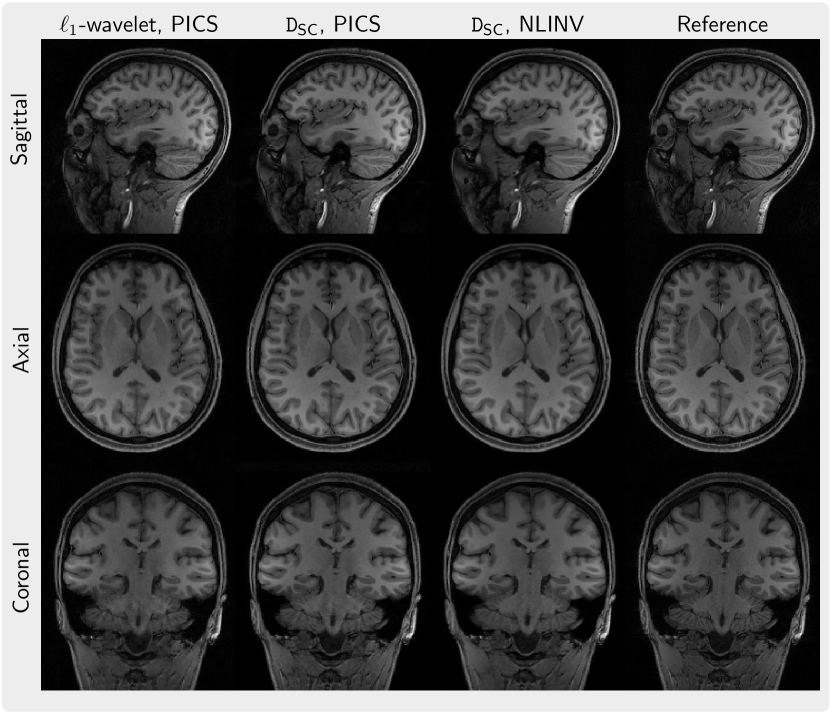

As an example, Figure 8 presents three slices in the sagittal, axial, and coronal planes for a 3D volume reconstructed using the diffusion prior DSC using PICS and NLINV in comparison to -wavelet regularization and a reconstruction by coil combination of Fourier-transformed fully-sampled k-space data. By visual inspection, the -regularized images appear to have reduced sharpness compared to the images regularized by the diffusion prior DSC while also having more noise.